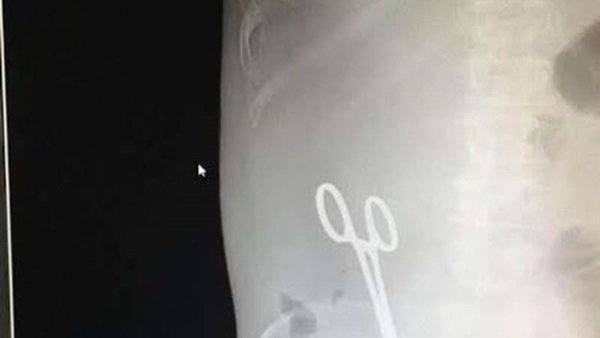

أخطاء طبية و آخرها طبيب ينسى المقص في بطن المريض

فتحت إدارة مستشفى الملك خالد في مدينة حائل السعودية، تحقيقاً مع طبيب،ب سبب اتهام مريض له بنسيان مقص طبي في بطنه بعد عملية سحب سوائل من المريض.

وذكرت صحيفة "عكاظ" أن المريض، الذي بث صور أشعة تبين وجود المقص داخل البطن، شعر بألم حاد في البطن، وحضر لطبيبه الذي طلب منه إجراء أشعة، وتبين وجود مقص العملية السابقة منسياً في بطن المريض، حيث قام الطبيب فوراً بإجراء عملية أخرى واستخراجه.